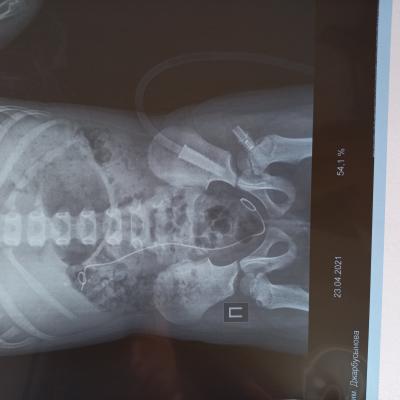

Здравствуйте! У моей дочери(5 лет)в феврале этого года обнаружили камни в почках фосфаты и оксалаты размером 1.6 мм и 0.6 мм, плотностью 1300 и 600 едХ. В марте была произведена операция по дробилению камня-ретроградная литотрепсия с установкой стент-катетора, в апреле трансуретральное устранение обструкции из мочеточника и почечной лоханки с заменой стент-катетора. Через неделю после выписки с больницы выпадает стент-катетор и в результате развивается гидронефроз. В начале мая опять же ставят стент-катетор и опять же он выпадает. В конце мая опять же производят операцию ЭУВЛ без установки стент-катетора. Последние снимки УЗИ показали, что камни ещё присутствуют в лоханке и в нижней чашки 7.6, 5.9, 5.8, 5 2,3.7, 4.9. Как вывести эти камни из почки и как можно выявить причину образований этих камней? Какие лекарства необходимо принимать, чтоб растворить камни?

Здравствуйте! Судя по представленным документам, Вашу дочь лечат высокопрофессиональные доктора и хирурги. При имеющейся ситуации вопрос о "растворении" конкрементов не идёт. Действительно, одномоментно вывести все фрагменты при естественных малых размерах мочевыводящих путей у ребёнка затруднительно. Поэтому приходится прибегать к неоднократным эндоскопическим процедурам, что, однако позволяет избежать более травматичного открытого хирургического вмешательства. Не исключено, что будет предложено очередное эндоскопическое вмешательство. К сожалению, вряд ли возможен вообще неинвазивный метод лечения в данном случае.